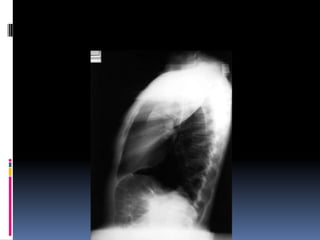

CXR - PA Vs AP view.

PA- the x-rays penetrate through the back of the

patient on to the film

AP-the x-rays penetrate through the front of the

patient on to the film.

 AP views make heart appear larger than it

actually is.

CXR - PAVs AP view. PA- the x-rays penetrate through the back of the patient on to the film AP-the x-rays penetrate through the front of the patient on to the film.